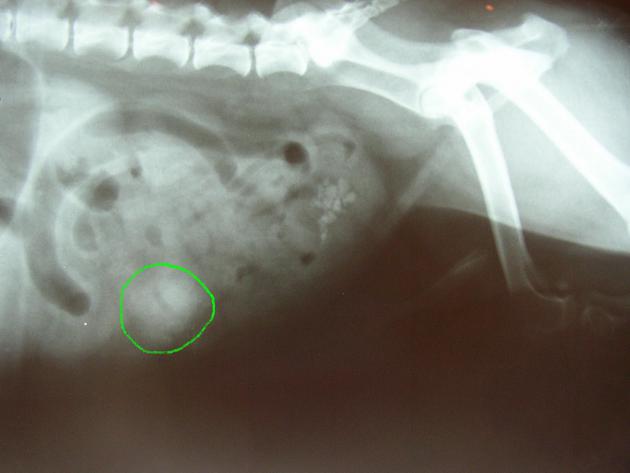

– La présence de certains corps étrangers peut être suspectée voire directement révélée par une radiographie simple: une dilatation de l’estomac et la présence d’air sur une radiographie abdominale de lapin feront très fortement suspecter la présence de trichobézoards tandis que des objets métalliques ou des os seront directement visibles sur le cliché radiographique de l’abdomen d’un chien.

en vert: corps étranger dans l’abdomen d’un chien (il s’agissait d’un morceau de caoutchouc)

(la radiographie révèle également la présence de calculs dans la vessie)